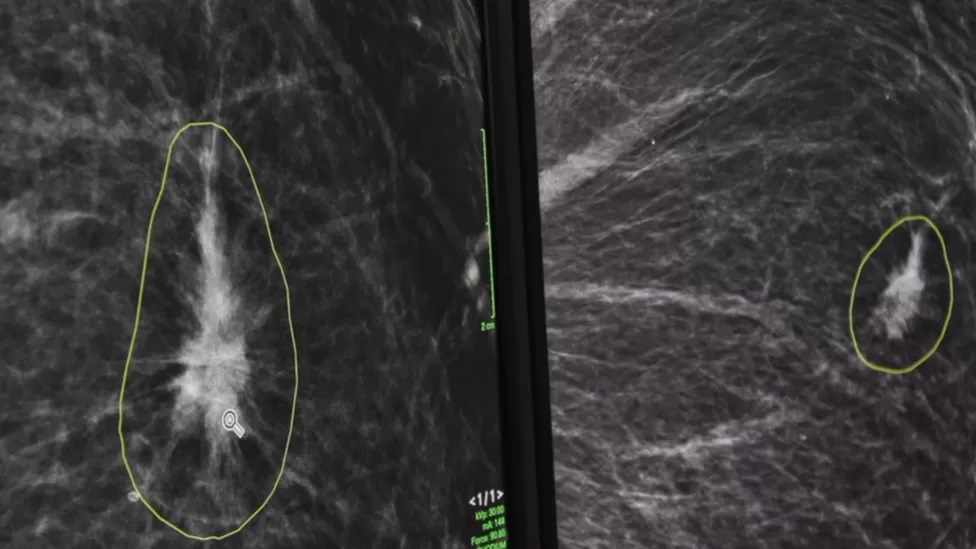

He showed BBC Click how the software works using anonymised mammogram results.

"What we're seeing now is a lady who's got mammograms on the left side and right side, you're looking for differences," he said.

By clicking a button, radiologists can view and check differences identified by the AI between the two scans.

Dr Lip pointed to one area circled by the AI software, identifying it as the main area of concern.